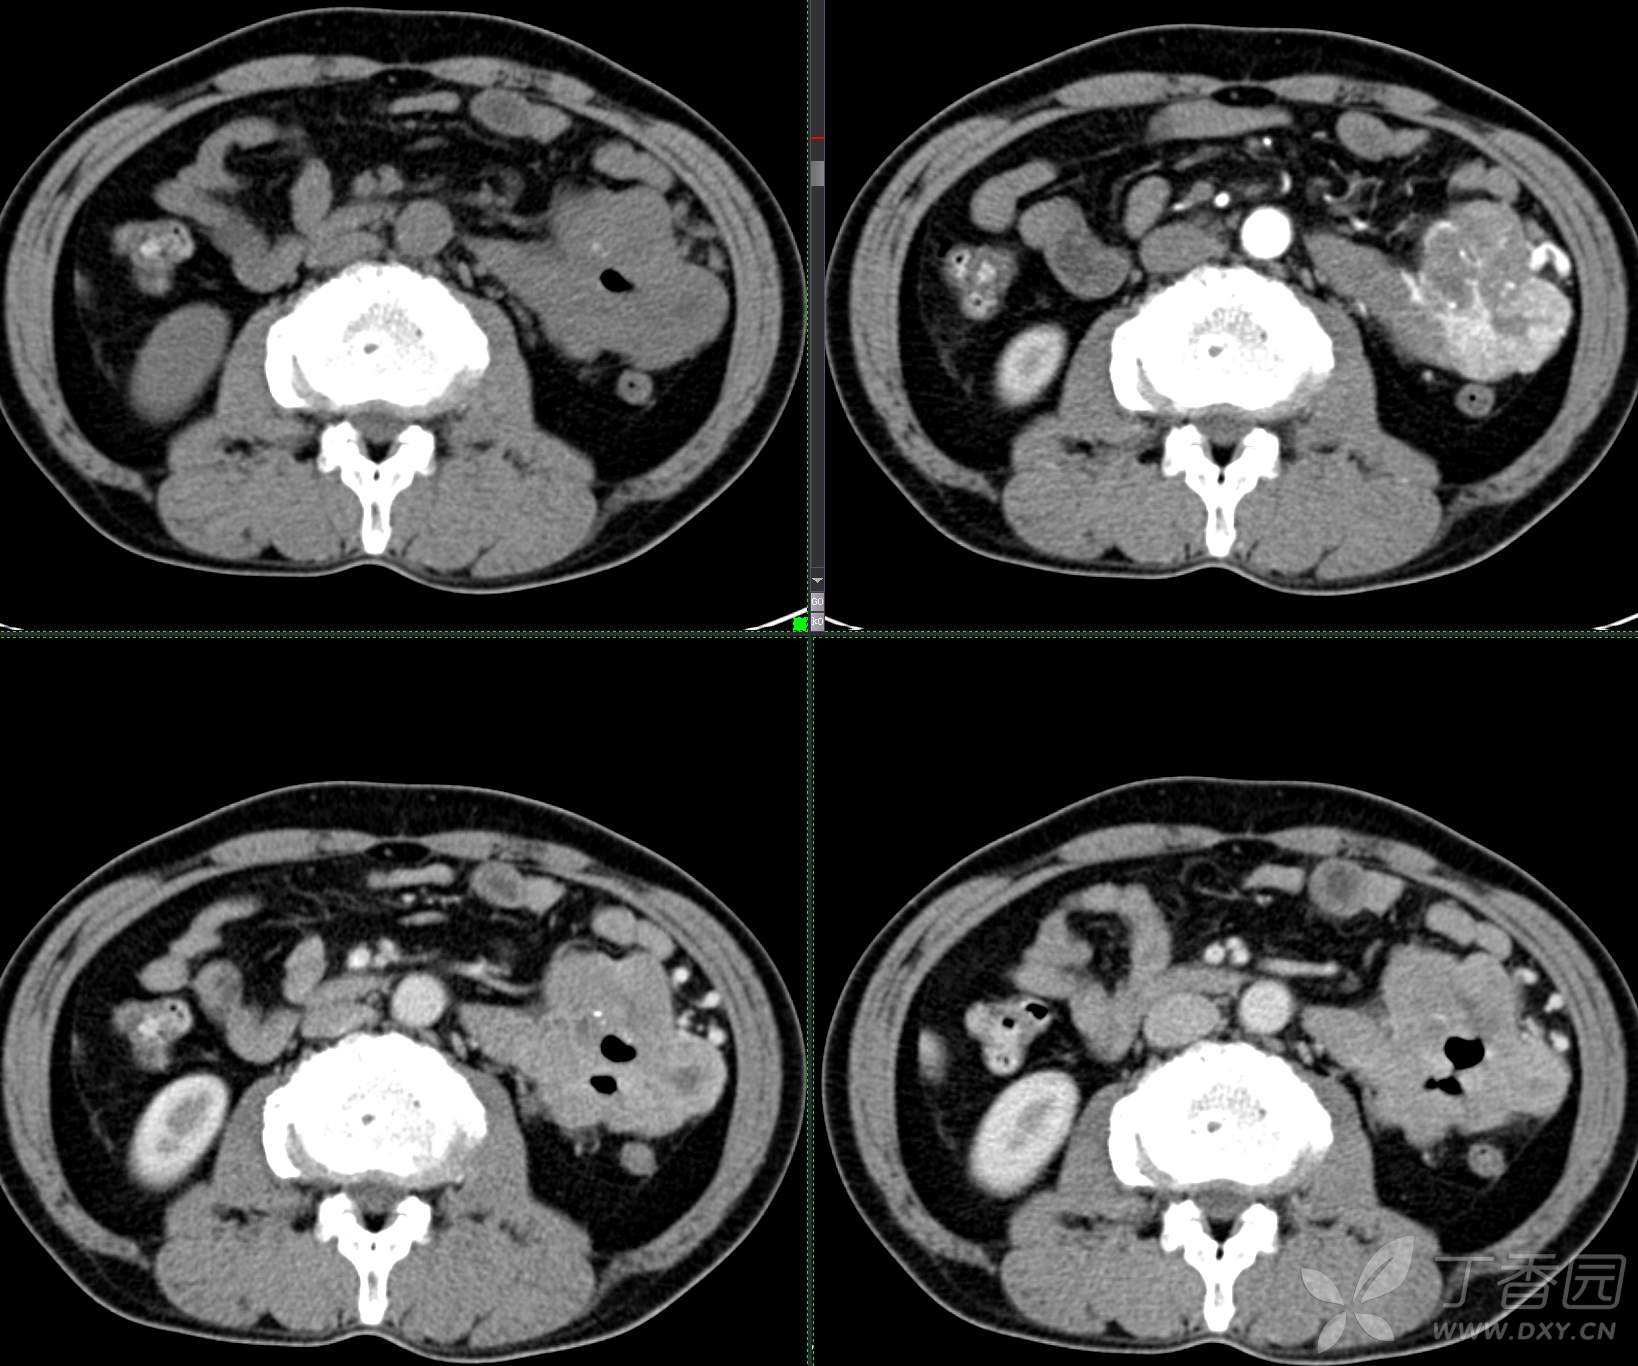

讨论:小肠病变,间质瘤?淋巴瘤?小肠腺癌?